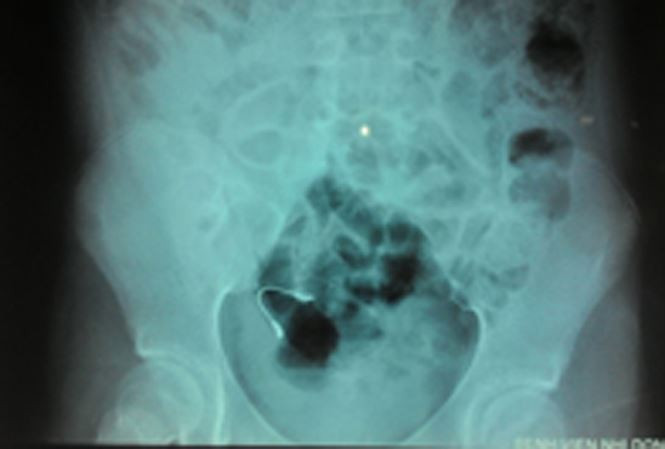

| Leah Kitchen suýt mất mạng vì bị miếng kim loại từ niềng răng rơi vào tim. |